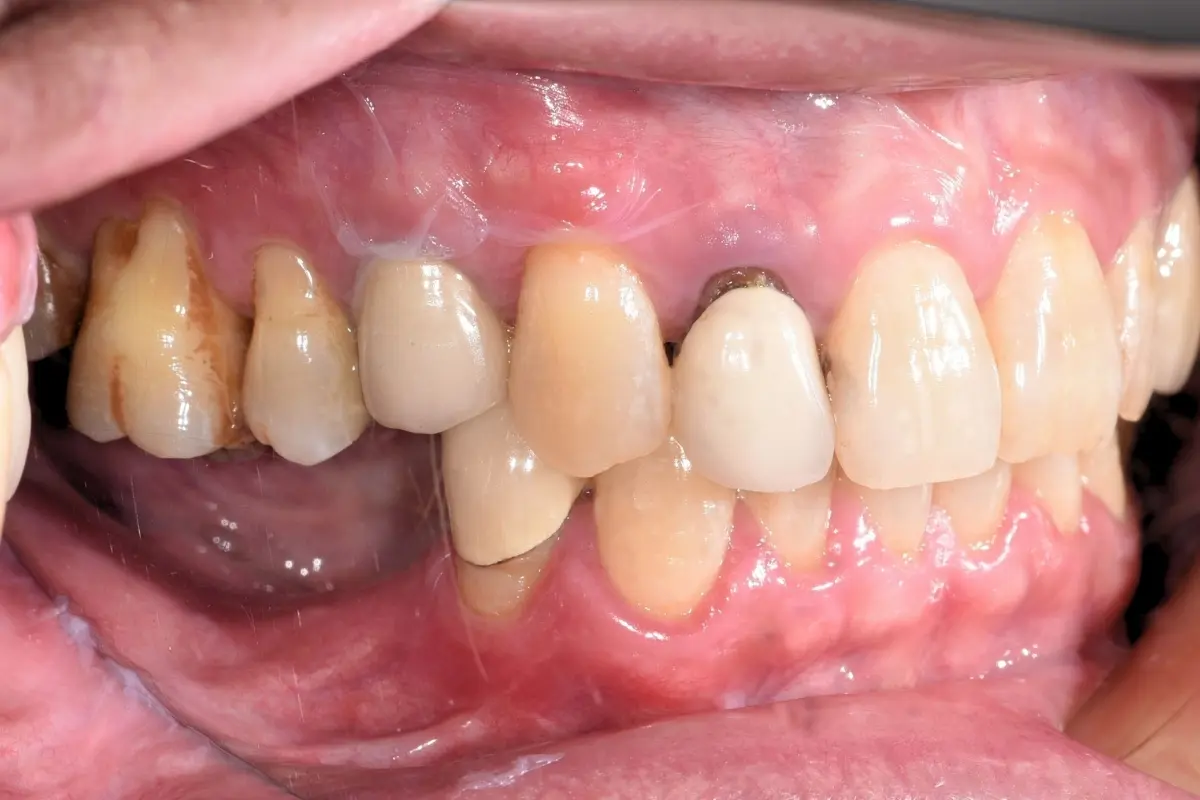

• 術前 21

術後 20

人工植牙

主治醫師

• 林明志

治療時間

約1年5個月

主訴

後牙長期缺牙,進食不便